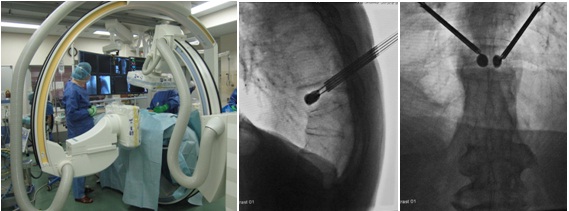

思春期特発性側弯症が高度に進行した症例です。最大側弯角度は113°であり、100°を超える側弯の手術は一般的に神経合併症が危惧されます。神経合併症を極力防ぐため、また侵襲を低減する目的で、同じ入院期間に2回に分けて段階的に矯正手術を行いました。1回目に最も側弯の強い箇所に対して側方から椎体間解離を行い、2回目に後方から全体のバランスが良くなるように慎重に矯正固定術を施行しています。

神経合併症はなく、術後の最大側弯角度は15°に改善(矯正率:87%)、背中の大きなコブも無くなっているのが分かります(赤矢印)。神経合併症が発生しないように慎重に手術を行うのは当然ですが、側弯を治すだけでなく横から見た姿勢を治すことにも留意しています。